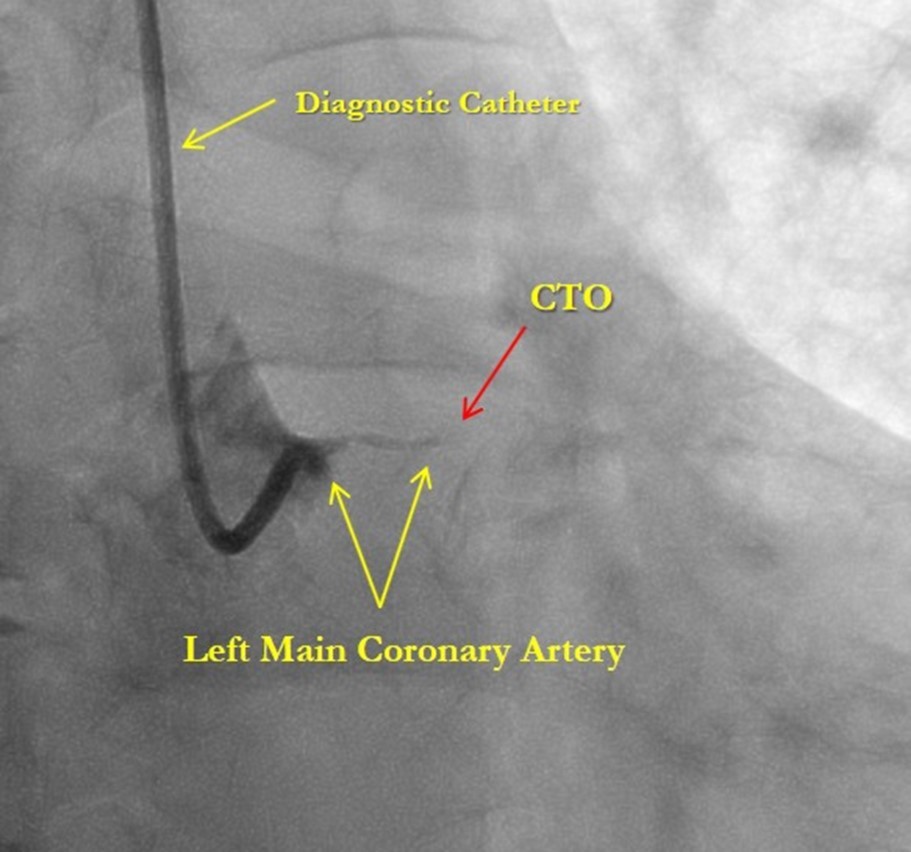

After medical treatment and comparable improvement in the patient's condition, expected risks were re-evaluated. After consulting with the patient and family members (they did not agree to the operation based on past experience) it was resolved to perform repeated CAG and to attempt revascularization of the LAD artery, (stenting). However, repeated CAG additionally revealed chronic 100% occlusion of the LMCA (Figure 1), and also CX occlusion, which was unexpected, and thereby significantly decreasing the likelihood of procedural success. In this case, the patient's heart was supplied only through the right coronary artery, which partially supplies the occluded left anterior descending and circumflex arteries through the contralateral collateral blood flow (Figure 2). Acute LMCA occlusion in most of the cases is fatal and survival is possible only in patients with a dominant RCA providing sufficient collateral formation.

Figure 1.Chronic total occlusion of the left main coronary artery

Chronic total occlusion of the left main coronary artery